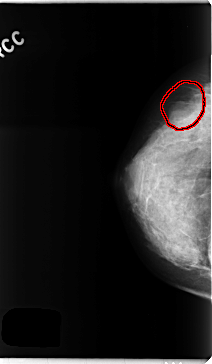

C_0257_1.RIGHT_CC

FILE: C_0257_1.RIGHT_CC.OVERLAY

TOTAL_ABNORMALITIES 1

ABNORMALITY 1

LESION_TYPE MASS SHAPE OVAL MARGINS OBSCURED

ASSESSMENT 4

SUBTLETY 4

PATHOLOGY BENIGN

TOTAL_OUTLINES 1

BOUNDARY